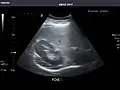

Right kidney

Kidneys: Right and left kidneys measure 11.5 cm and 12 cm in length respectively. No hydronephrosis. Small left lower pole kidney cyst.